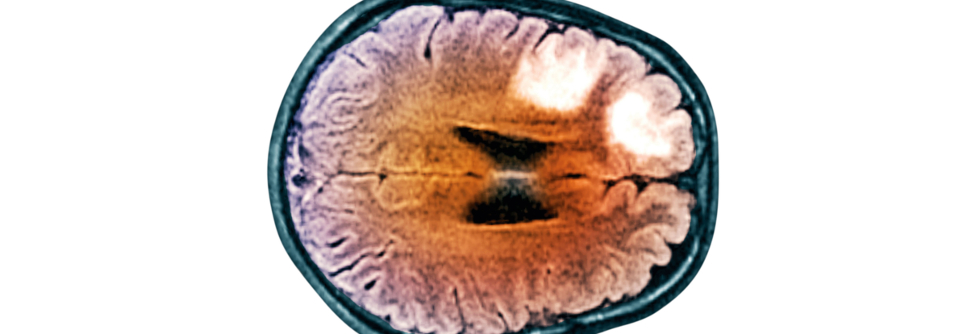

Zu selten kommen gezielte Therapien unter anderem bei Fatigue oder kognitiven Störungen zum Einsatz. Zu selten kommen gezielte Therapien unter anderem bei Fatigue oder kognitiven Störungen zum Einsatz. © fran_kie – stock.adobe.com

Die meisten Patienten mit Multipler Sklerose erhalten heute eine krankheitsmodifizierende Immuntherapie. Doch die typischen Symptome wie Fatigue, kognitive Beeinträchtigungen oder Blasenstörungen werden noch immer unzureichend behandelt.